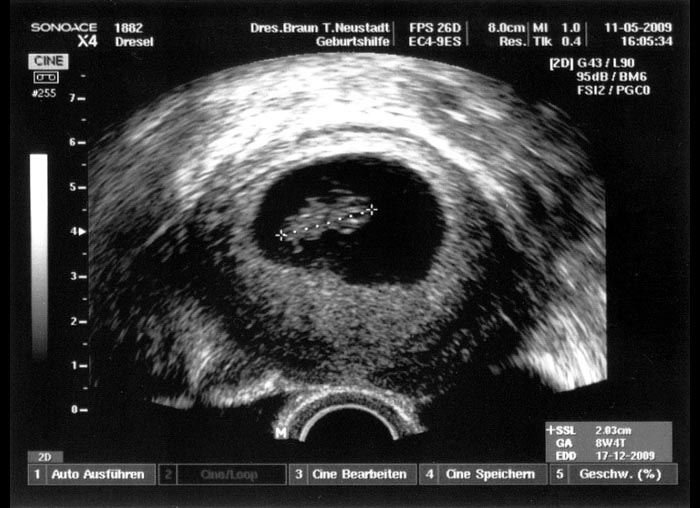

2. Ultraschallaufnahme